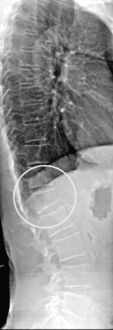

EXAMINATION

Whilst some fractures may be painfully obvious others may be detected only after careful examination and investigation. Thoracic kyphosis (Fig. 20.5A,B) may develop gradually as one vertebra after another fractures (or is compressed) or more suddenly if one or more severe wedge fractures occur. The development of the Dowager’s hump is a well recognised but late sign of osteoporosis. As this becomes more pronounced, the lower ribs impinge on the iliac crests and the abdomen protrudes. An exaggerated cervical lordosis is apparent when the patient attempts to look straight ahead. Evidence of a previous wrist fracture may also be seen such as the classical dinner fork deformity of a Colle’s fracture. A shortened externally rotated leg is highly suggestive of a fractured neck of femur.

image

Figure 20.5 (A), (B) Thoracic kyphosis. (Dowager’s hump) (A) Marked thoracic kyphosis due to multiple osteoporotic fractures in an elderly woman with (B) corresponding radiograph.

With permission Hochberg MC (2008). Elsevier.